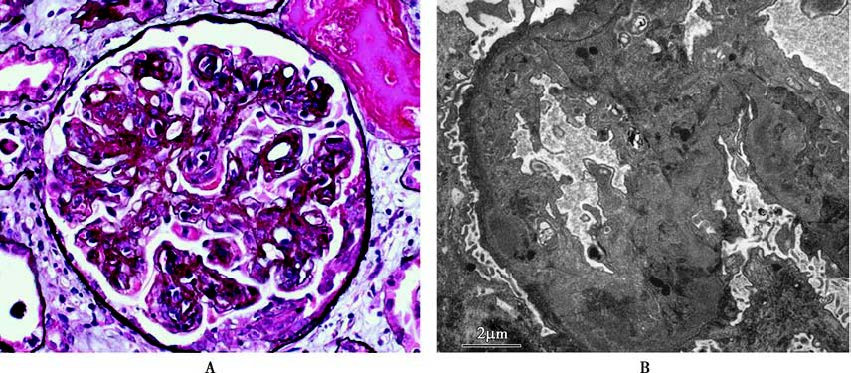

Figure 7 Pathological images of mesangiocapillary glomerulonephritis

A. "Double contour" appearance of glomerular capillary loops in light microscopy (silver staining);

B. Electron-dense deposits visible in the mesangial area and subendothelial region in electron microscopy.

The pathological changes observed in light microscopy frequently include diffuse and severe proliferation of mesangial cells and mesangial matrix, which may extend between the glomerular basement membrane and endothelial cells. The GBM shows layered thickening, resulting in a "double-contour" appearance of the capillary loops. Immunopathological examination typically reveals granular deposits of IgG and C3 along the mesangial regions and capillary walls. Electron microscopy shows electron-dense deposits in the mesangial regions and beneath the endothelium.